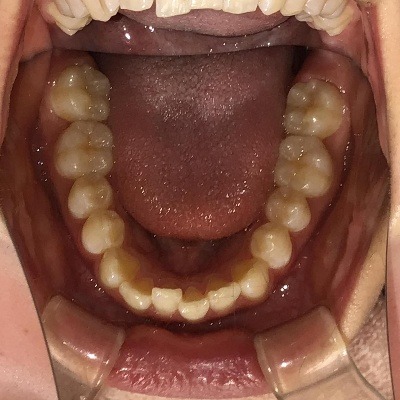

• BEFORE

症例集 インビザライン 下顎

矢印

AFTER

下顎